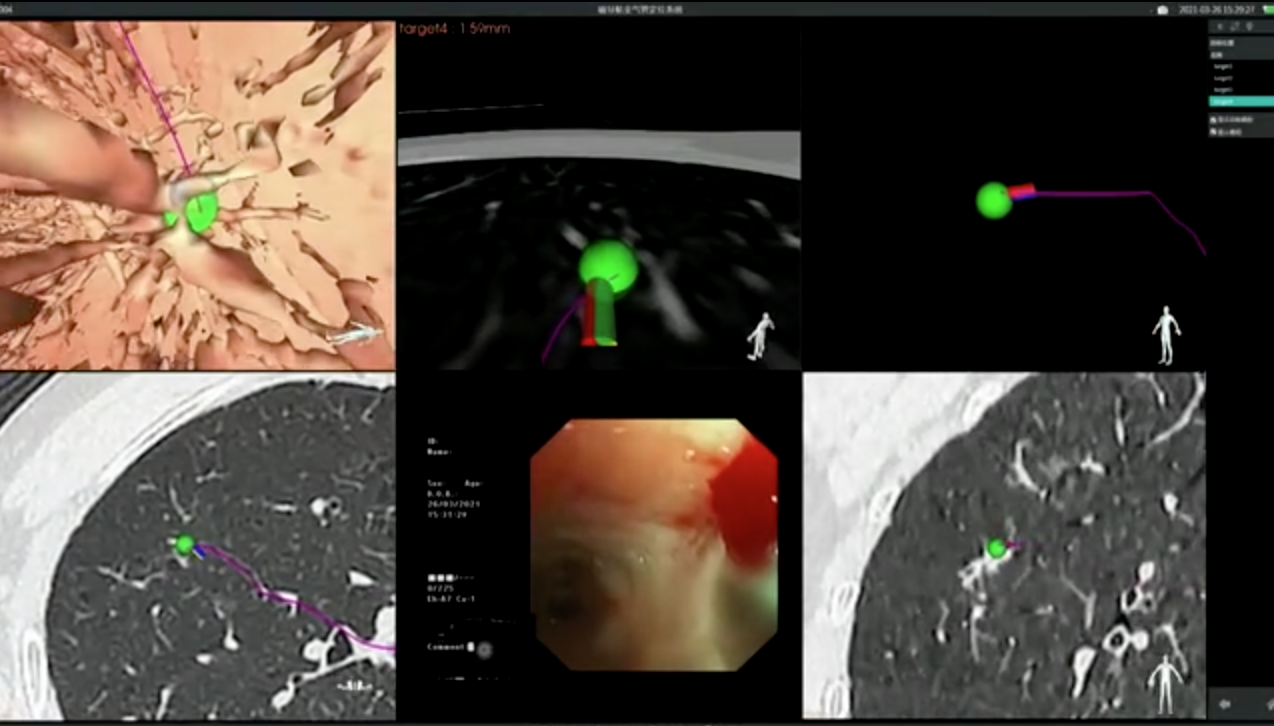

3月26日,由呼吸与危重症医学科蒋军红主任带领介入与血管外科团队对这位患者进行了磁导航支气管镜检查,顺利完成标本取样,并在术中对病灶进行了精准消融。术后,病理提示为原位腺癌。磁导航支气管镜检查精准定位,大大提高了诊断率,同时最大限度保留肺部功能,提高了患者的生活质量。

电磁导航支气管镜是一种以电磁定位技术为基础,结合计算机虚拟支气管镜与高分辨率螺旋CT的特点,经支气管镜诊断的新技术。通俗理解就是我们肺部的支气管像道路一样错综复杂,而肺部的一些病变如结核及肿瘤等病灶是我们想要到达的目的地。磁导航就如同星导航系统,可以给我们选择快捷而准确的线路指引我们到达目的地。

电磁导航支气管镜被认为是“肺癌诊断新利器”。相较于普通气管镜有以下优点:1、范围广:全肺可达,包括肺周边及深部纵隔淋巴结。2、诊断率高:精准定位,且可通过多样化的活检工具进行采样,并可多点、多次采样,大大提高了诊断率。3、安全性高:电磁导航支气管镜是经人体自然通道到达肺内病灶,属于相对无创,减少气胸风险及有创手术的各种并发症4、治疗多样化:对于病灶还可进一步进行标记,利于微波、消融、放疗等精准治疗,最大限度保留肺部功能,提高生活质量。对于多种疑难疾病比如性质不明纵隔淋巴结、疑诊肺结核及淋巴结结核,电磁导航支气管镜诊断系统可以替代纵隔镜及胸腔镜活检,大大降低了创伤及风险。